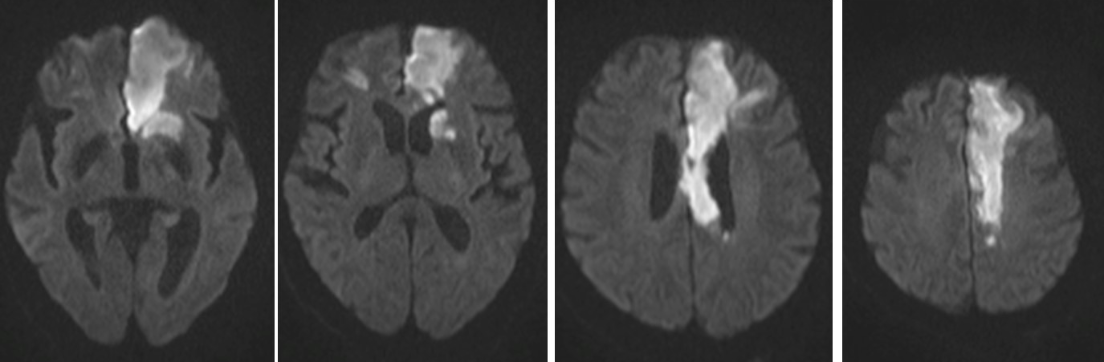

Basal Ganglia Stroke

ACA Stroke

MCA Stroke

PCA Stroke

• Different strokes affect distinct brain areas depending on the artery involved.

• Early recognition of symptoms is crucial for timely intervention.

• Understanding the arteries helps predict outcomes and guide treatment.